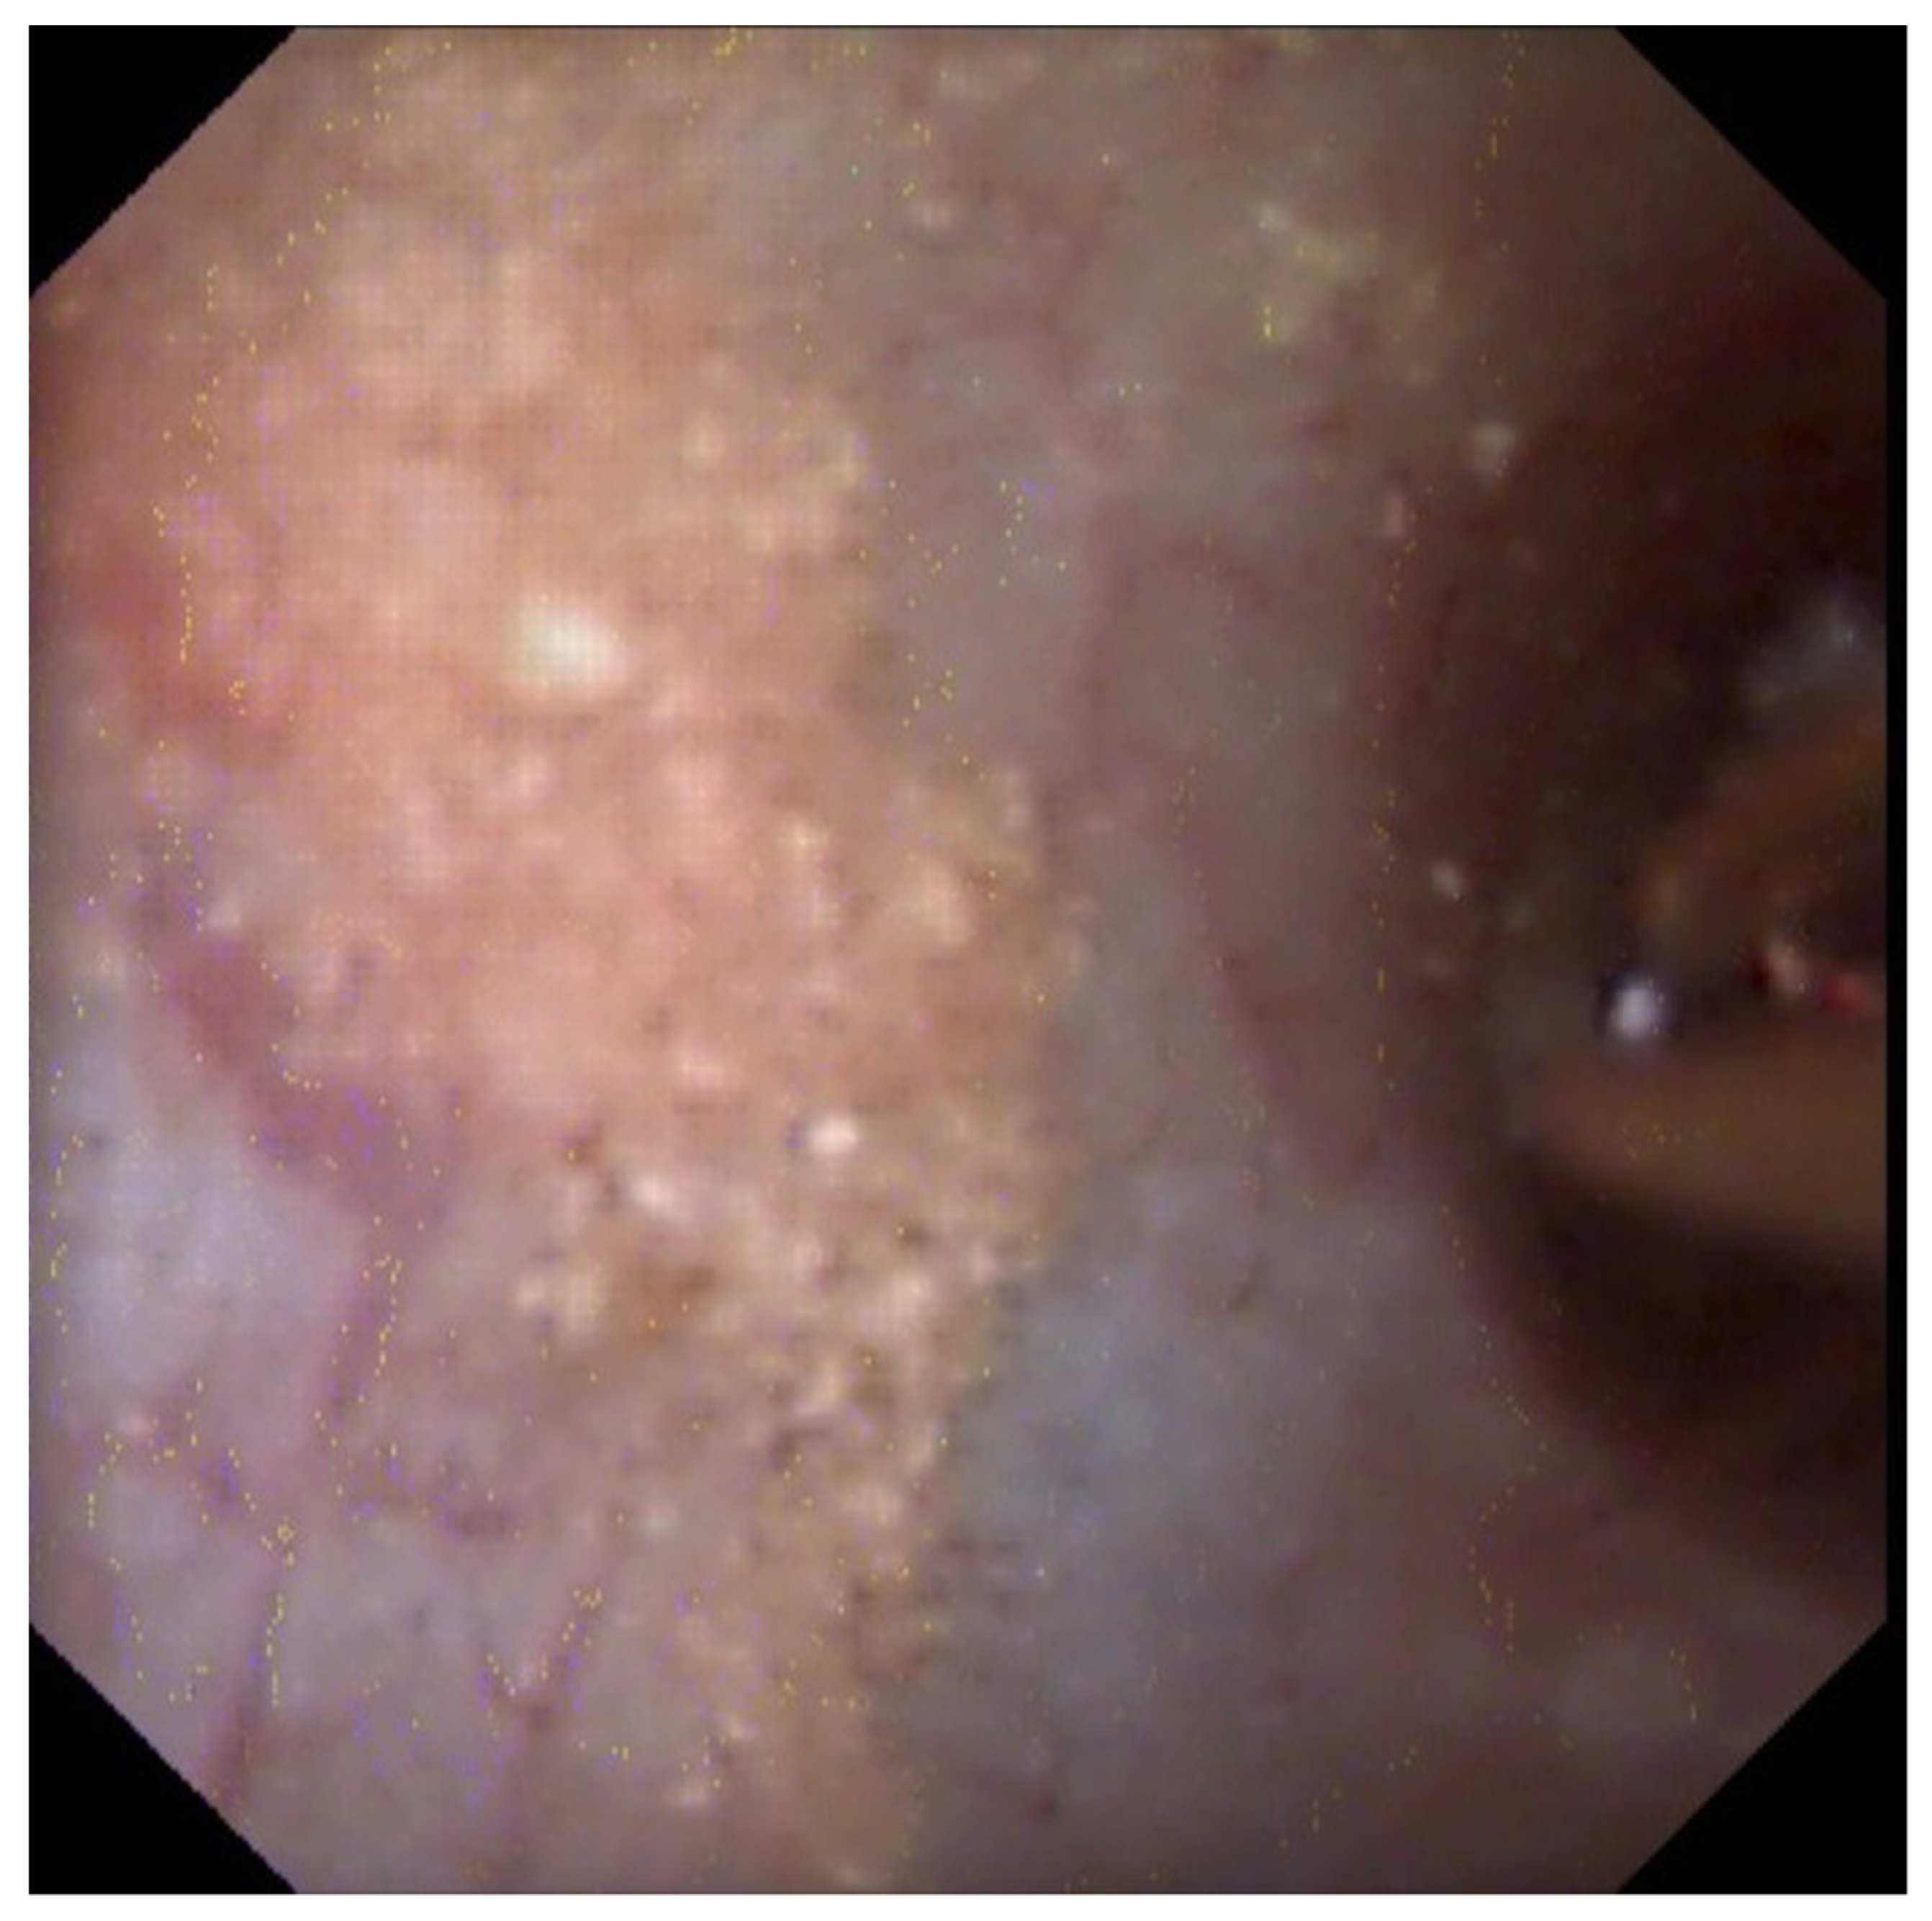

The observation of “erosions” or “pits” at the tip of the papilla and the presence of anchored COM stones were also frequent (55.7% and 18.2%, respectively) and correlated with the amount of Randall’s plaques (Figure 3) [23,24,25]. They resulted from a dietary cause (especially low fluid intake) in most cases [36,37,38,39].

Figure 3.

Lithogenesis on Randall’s Plaques (RP). (A) Papilla with RP. (B) Papilla with anchored stones and erosion secondary to RP. 1—RP originate from the basement membranes of thin loops of Henle, spread with CA in the surrounding interstitium, and may erode the epithelium. Their aspect is a not well delineated infiltrate of the papilla. 2—Erosion or pit, that is the footprint of a previous anchored stone drop off. 3—Typical COM anchored stones, owing to the small size of the COM crystals that are the first able to combine with the plaques.